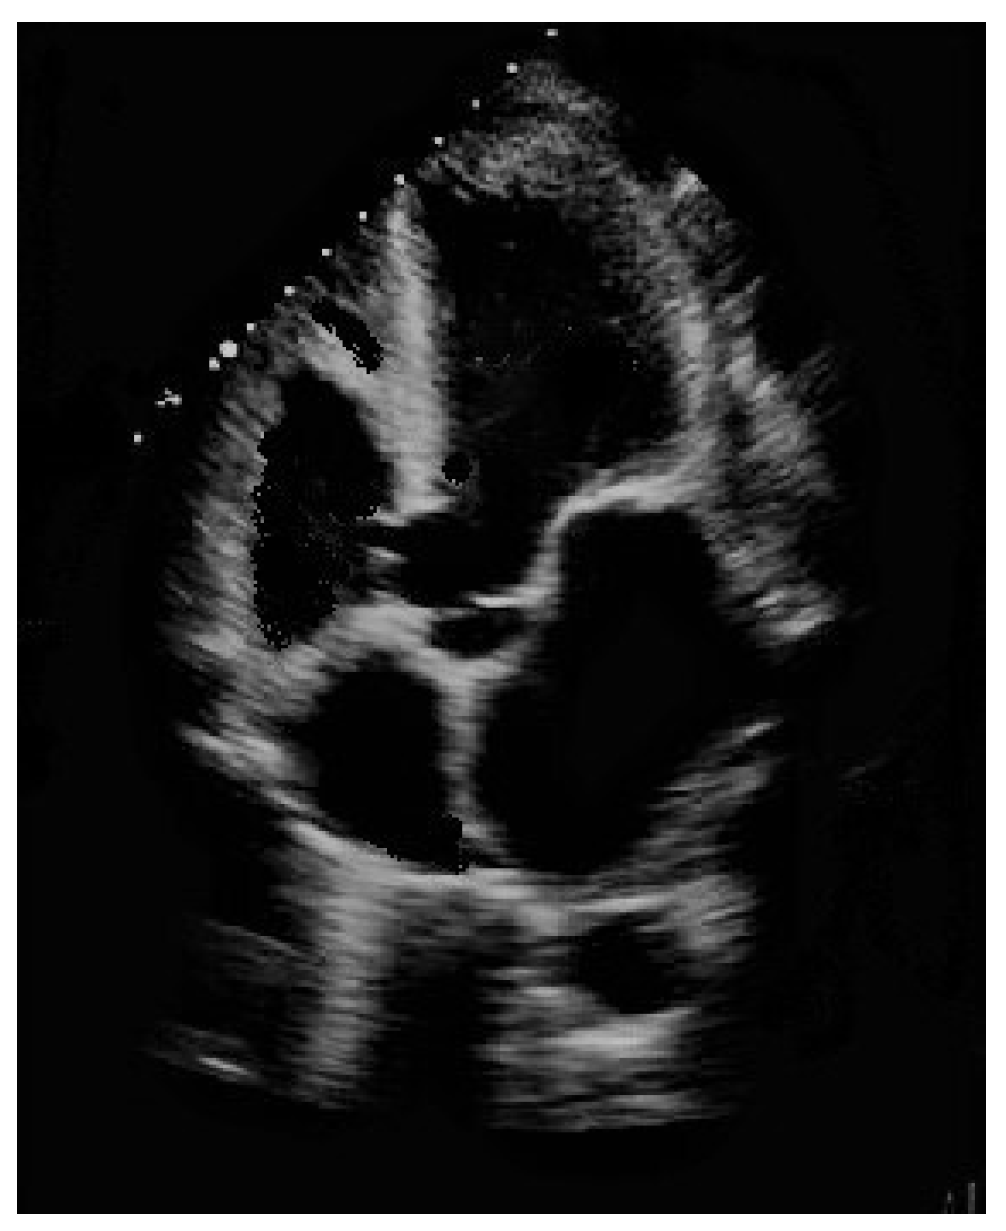

Haemoglobin levels in all patients in the needing intervention group was less than 12.7 g/dL (Figure 2).

Anemic infants have ventricular septal defects more frequently than those with normal haemoglobin levels [24]. Haemoglobin is capable of promoting tissue regeneration, cells proliferation and wound healing, as both processes rely heavily on oxygenation. There is no doubt that an adequate supply of nutrients and oxygen to regenerating cells is crucial for their survival and functional maintenance [25].The natural healing of perimembranous ventricular septal defects involves a series of different mechanisms, including tissue growth from the remnant membranous septum or tricuspid valve and adhesion of tricuspid valve leaflets [19]. Tissue regeneration seems to be influenced by haemoglobin-related tissue oxygenation in a number of clinical scenarios [26]. Moreover, correct blood viscosity represents another factor of importance in promoting the adhesion of tricuspid valve leaflet to the tissue surrounding perimembranous ventricular septal defects [19]. Blood viscosity is intricately linked to haemoglobin content: the higher the haemoglobin levels, the higher the hematic viscosity and vice versa [27]. Anaemia, and subsequently reduced blood viscosity, may exert a negative influence on the above-stated adhesion, thus impinging on the natural resolution of ventricular septal defect [28]. Not only, but left-to-right shunt across ventricular septal defect may lead to a volume overload to the lungs, as expressed by QP/Qs ratio higher than 1.1, with consequent further dilution of haemoglobin [29]. Major and minor forms of thalassemia and other types of anaemia are considerably diffuse in Sardinia, i.e., the Italian region where the research was carried out, which may have negatively affected the number of self-healing patients in our cohort [30]. Our research showed a significantly lower prevalence of anaemia in the self-healing group than in those needing intervention. Our findings also suggest a value of 12.7 g/dL in haemoglobin content, above which level the self-healing of ventricular septal defect is unlikely. Overall, as confirmed also at multivariate analysis, haemoglobin blood concentration seems to influence the natural history of ventricular septal defect, and improvement of anaemia through supplementation of iron intake might represent a simple and reliable method of promoting the spontaneous healing of perimembranous vetricular septal defects [31].

Figure 2. All the patients in the study whose perimembranous ventricular septal defect did not heal by itself had a haemoglobin level less than 12.7 g/dL.